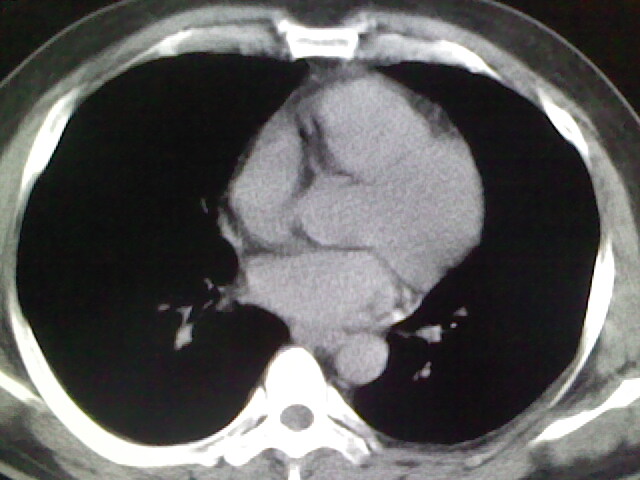

标题: CT17932:临床怀疑肺栓塞

男,34岁,自觉右侧胸痹,胸闷3天余

右侧肺动脉似见密度稍低影,请在机器的薄层上再看看有没有充盈缺损。